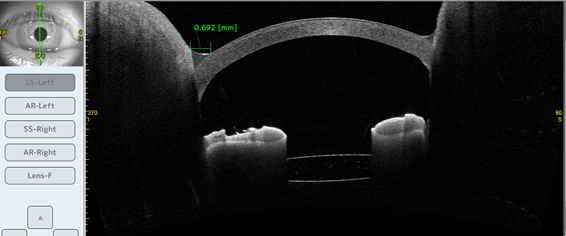

前眼部の正確な形態情報から患者さんに適したICLレンズサイズ情報を提供します。